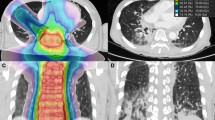

On the basis of postoperative CT images, we performed dosimetric evaluations of GTV and adjacent OARs by DVH (dose-volume histogram) (Fig. 2). We used D90 as the evaluation index for GTV. The OARs were evaluated with the parameters used in prostate brachytherapy, including D0.1cc, D2cc, and Dmean (dose to the most exposed 0.1 cc and 2 cc volumes of OARs, and mean dose to OARs)13,14. The OARs included the lung, blood vessels, spinal cord, esophagus, trachea, heart, and skin.